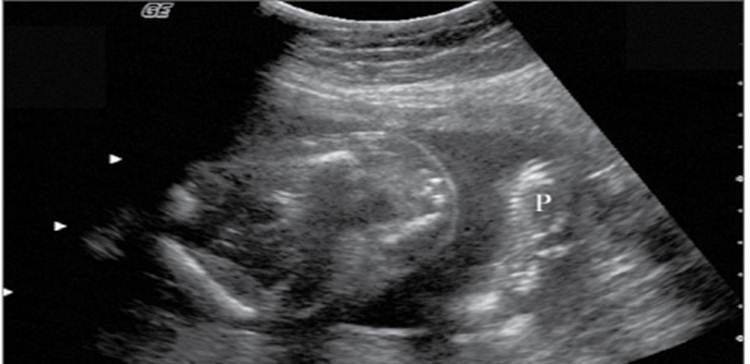

Placenta previa

Scalp edema